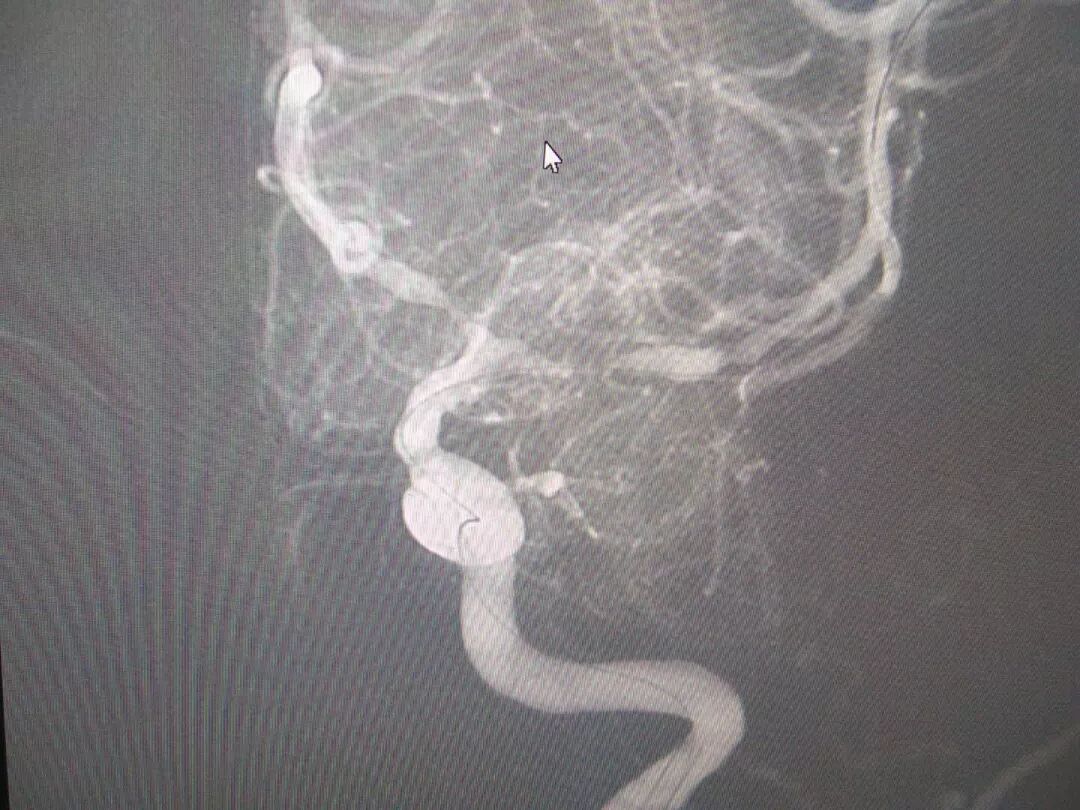

5月21日,一位言语不利2天的患者王某入住郑州中康医院神经内科一病区。入院后进行头部磁共振检查,结果显示:脑梗死。后5月24日进行全脑血管造影,造影结果显示:左侧大脑中动脉M1段分叉上下干重度狭窄。医师建议进行介入手术治疗,于6月4日下午召开了术前讨论,经讨论分析后,患者情况适合进行手术治疗,与家属沟通后,家属同意手术治疗。

图片

(术前左侧大脑中动脉造影)

6月5日上午,由介入导管室张少雷主任亲自主刀,在介入导管室行“超选择左侧大脑中动脉支架植入术”,手术历时2个小时,手术过程顺利,术后转入卒中监护室观察2天后,于6月7日下午转至普通病房治疗,患者愈后良好,家属表示满意。